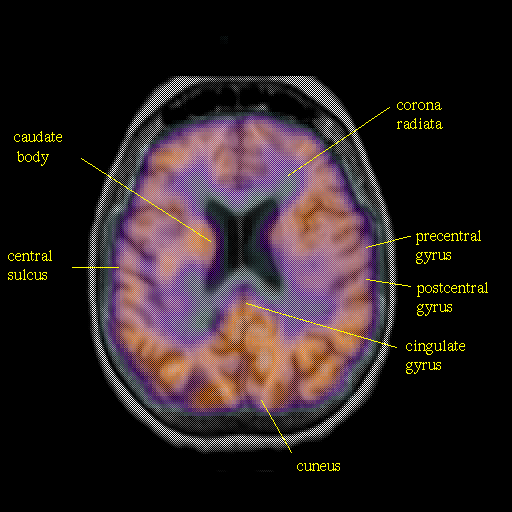

overlay: Slice 34

Slice 34

Pointers

Labeled